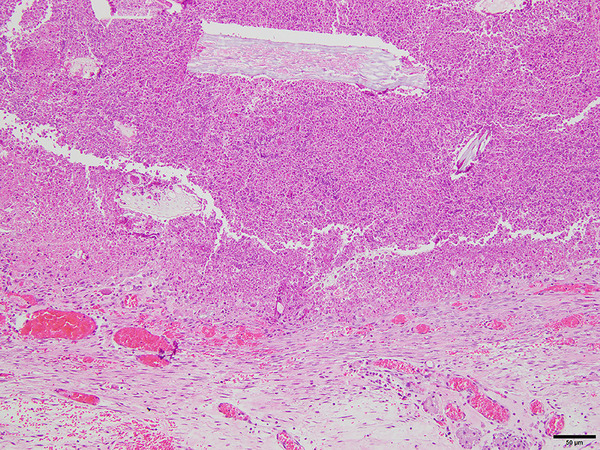

Results: Medical records were available for a total of 2128 rabbits, with 13 confirmed cases of intraabdominal abscess. Twelve cases considered eligible for this study were reviewed. Median age of the rabbits at onset was 18 months. Rabbits comprised 7 males (1 castrated) and 5 females (3 spayed), with 9 Lop-eared, 2 Netherland Dwarf and 1 Mini Rex. Common clinical signs were anorexia, decreased activity and abnormality of fecal production. Abdominal ultrasound and radiography revealed intraabdominal lesions in 12 and 7 cases, respectively. Exploratory laparotomy revealed intraabdominal abscess in all cases. Abscesses arose from the vermiform appendix in 6 cases and were associated with previous gastrointestinal perforation in 3 cases. The abscess was excised or incised with irrigation of the intraabscess cavity and administration of antibiotics. Nine cases showed an uneventful outcome (median survival time, 1044 days), including five cases showing growth of residual intraabdominal abscess.

Conclusions: Intraabdominal abscess in rabbits is commonly associated from the vermiform appendix and previous gastrointestinal perforation. Surgical intervention for intraabdominal abscess along with antibiotic therapy appears effective.